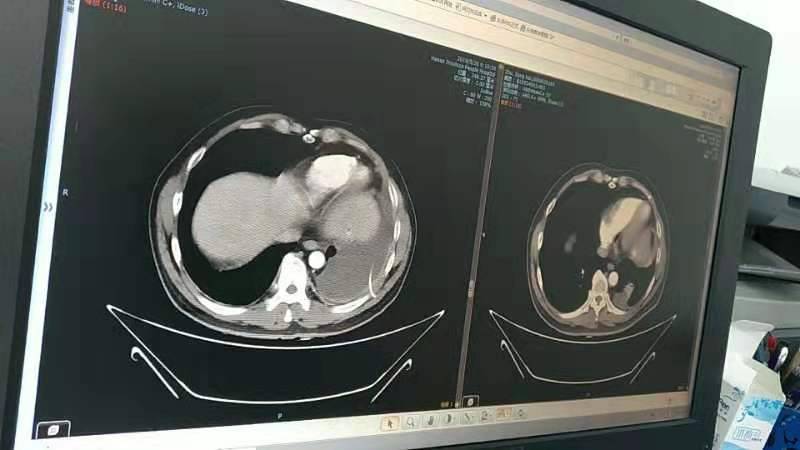

(以下两张照片左为七月,右为八月)

看图片是明显好转了。